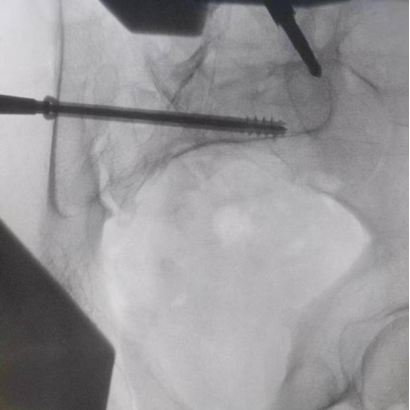

圖為透視下見(jiàn)置入的骶髂螺釘,位置、長(zhǎng)度精準(zhǔn),無(wú)絲毫偏差